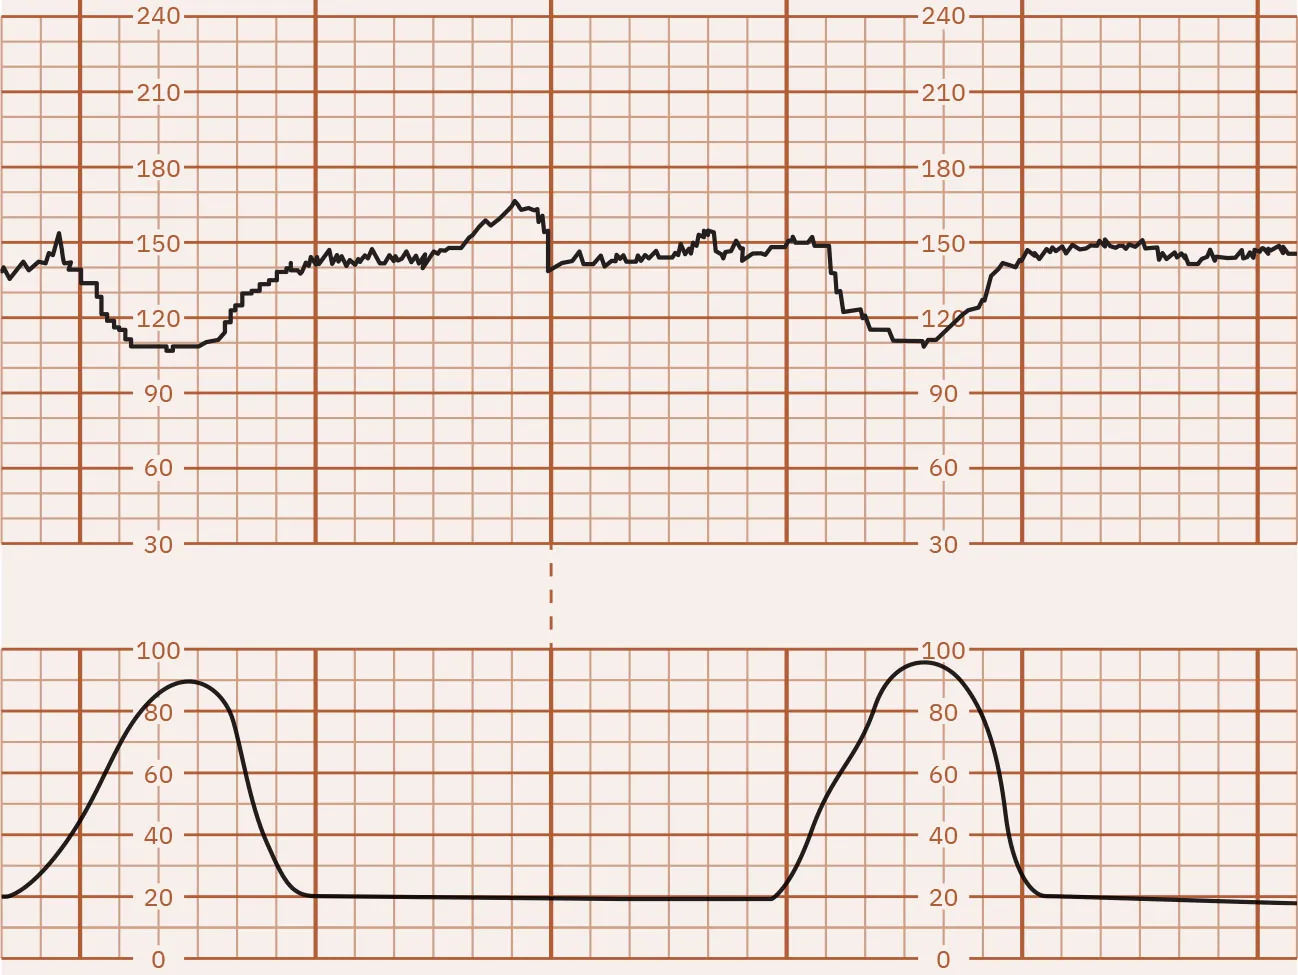

Decelerations in the FHR below the baseline that start during a contraction and continue after completion of the contraction are called late decelerations. Figure 16.12 illustrates late FHR decelerations. Late decelerations are nonreassuring and almost always indicate fetal hypoxia. They are associated with uteroplacental insufficiency, a lack of oxygenated blood coming from the uterus to the placenta to the fetus. During a contraction, the decrease in oxygen to the fetus causes a deceleration that begins late in the contraction. The nadir, or lowest point, of the deceleration is after the peak of the contraction. Another common cause of late decelerations is tachysystole (contractions occurring too frequently or lasting longer than 2 minutes), often seen with the use of oxytocin (Pitocin). Spinal or epidural anesthesia causes hypotension leading to hypoperfusion to the placenta, producing late decelerations. Other causes of late decelerations are hypertension, postmature placenta, placental abruption, and anemia. Late decelerations, like early decelerations, are often repetitive, forming a pattern.

Fetal heart rate reading indicating late decelerations.

Figure 16.12 Monitor Tracing Showing Late Decelerations of the FHR The FHR decreases during the contraction and does not return to baseline until after the contraction ends. These are defined as late decelerations. (attribution: Copyright Rice University, OpenStax, under CC BY 4.0 license)